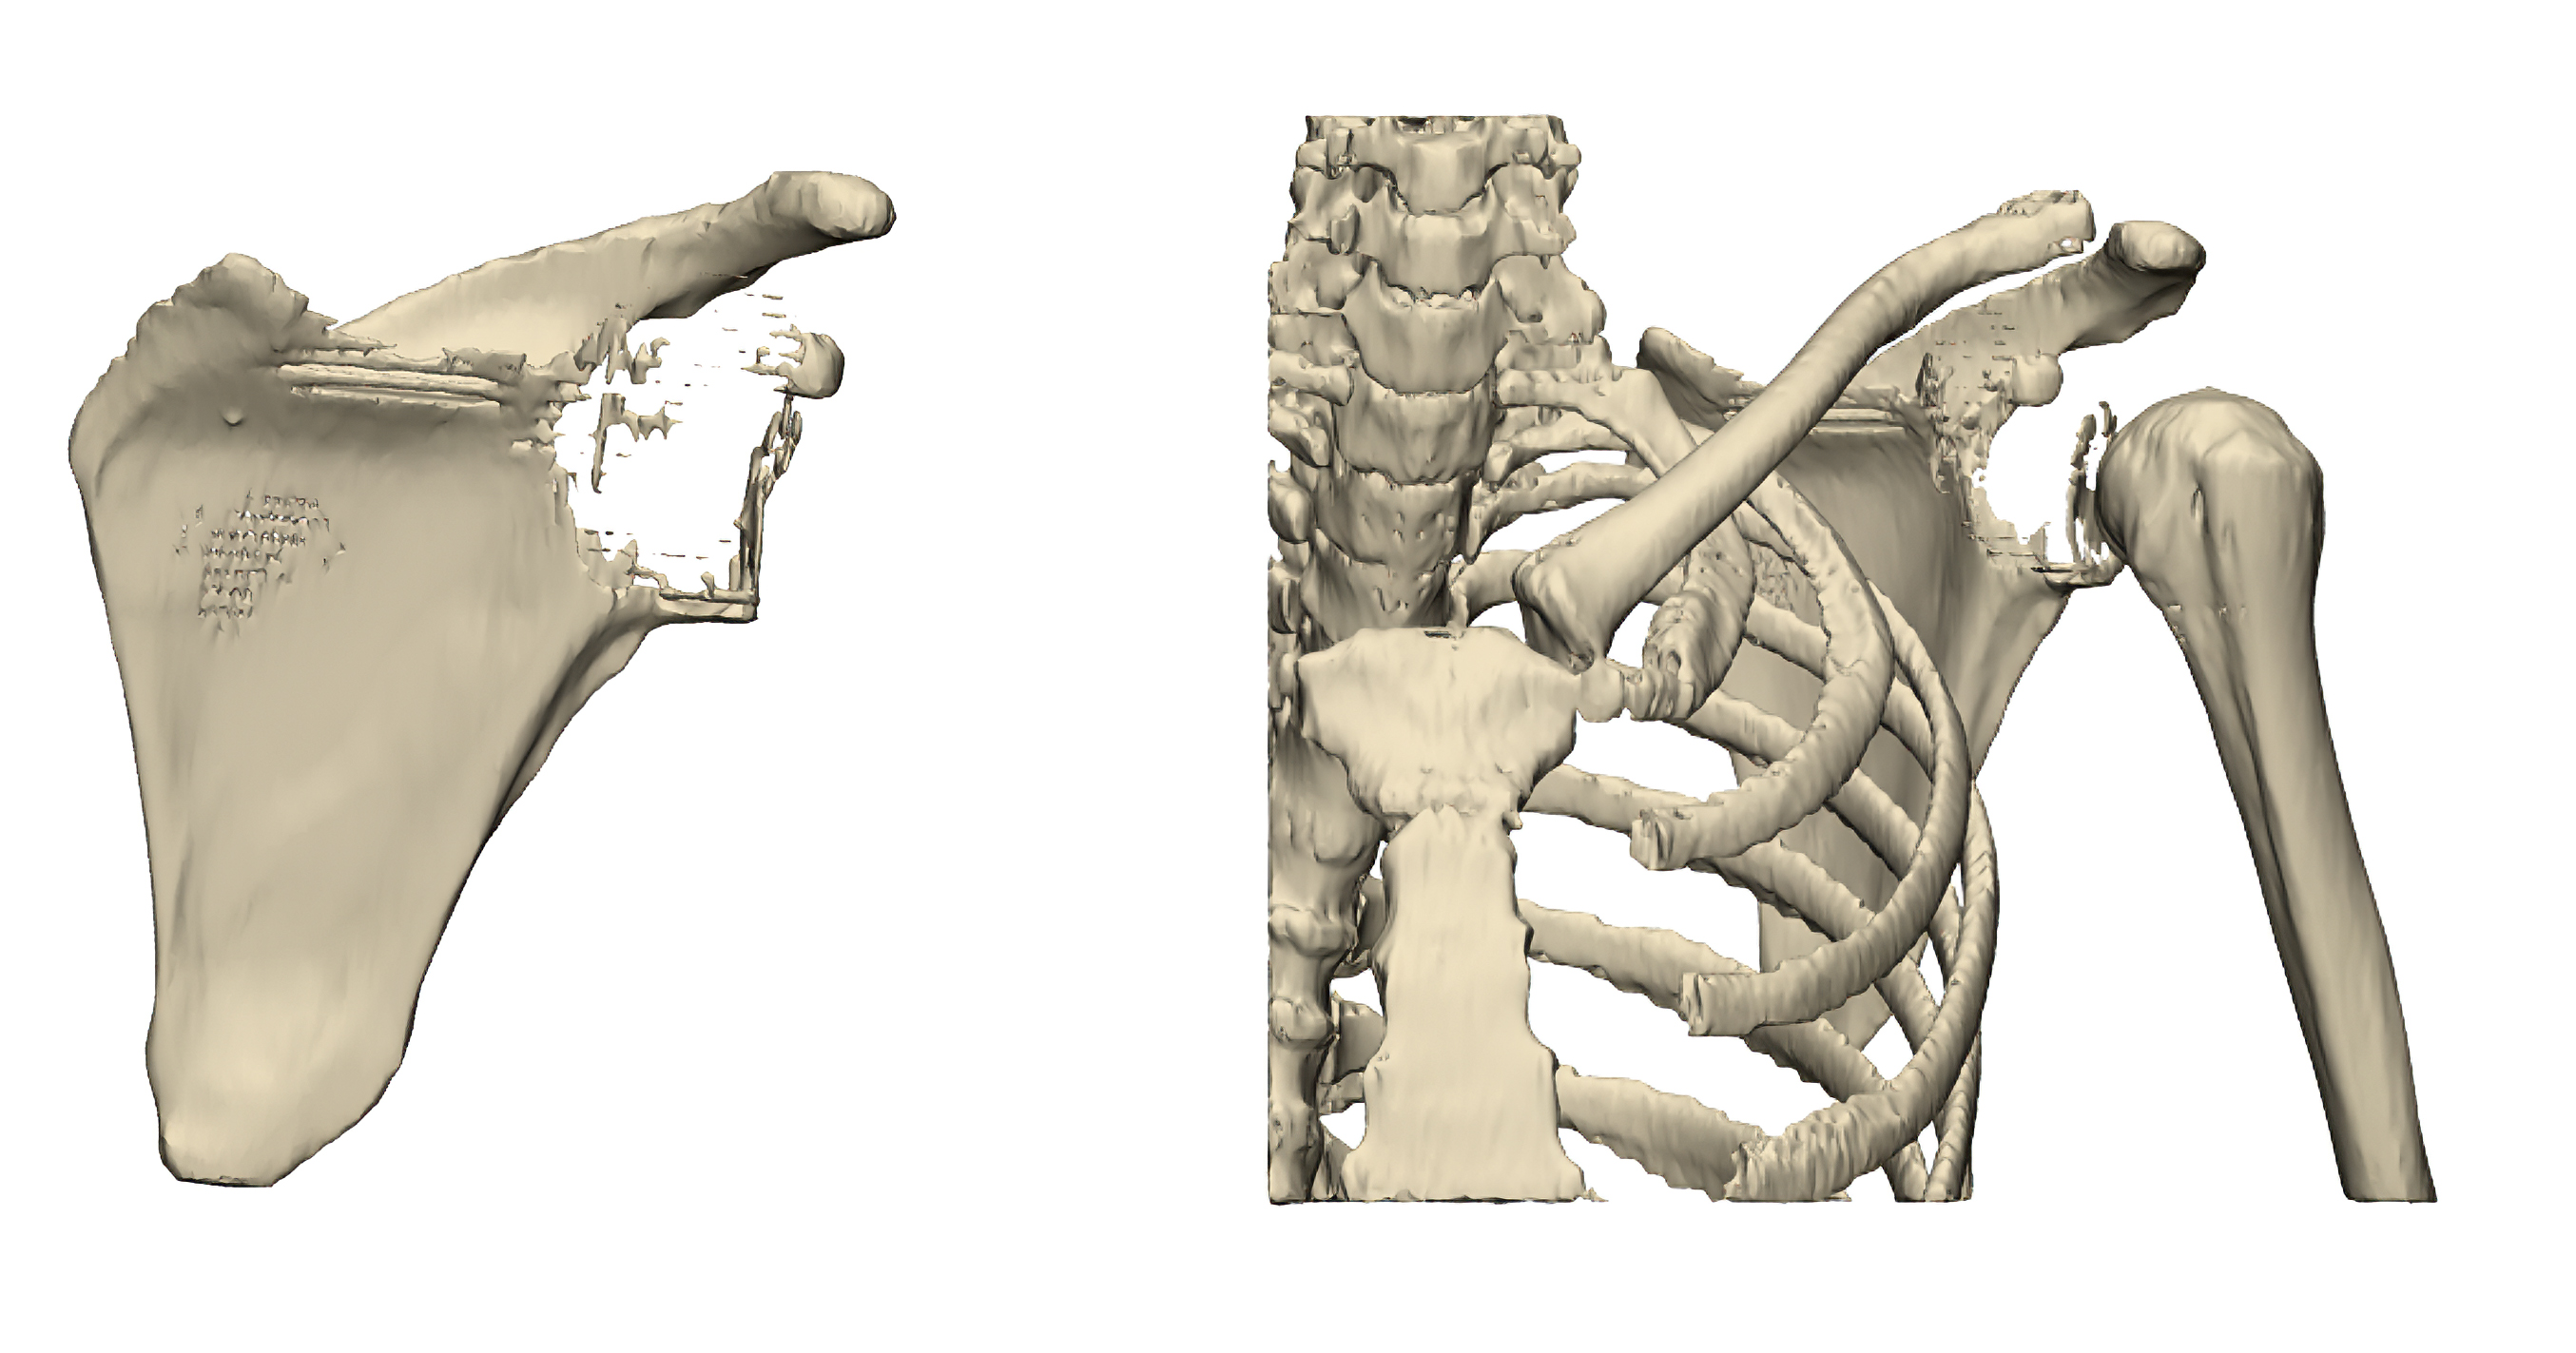

Preoperative 3D reconstruction demonstrating extensive tumor involvement of the left scapula.

The patient, over 35 years of age and taller than 160 cm, was diagnosed with a high-grade osteosarcoma of the left scapula. Preoperative imaging revealed extensive tumor involvement of the scapular body, making partial resection oncologically unsafe. A total scapulectomy was therefore indicated.

The clinical challenge extended far beyond tumor removal. The scapula serves as the anchoring platform for multiple muscle groups and provides the foundation for glenohumeral articulation. Its loss disrupts load transfer, alters the center of rotation, and compromises shoulder stability. The reconstructive objective was therefore to re-establish a stable articulation, allow reliable soft-tissue reattachment, and optimize biomechanical balance while maintaining oncologic safety.